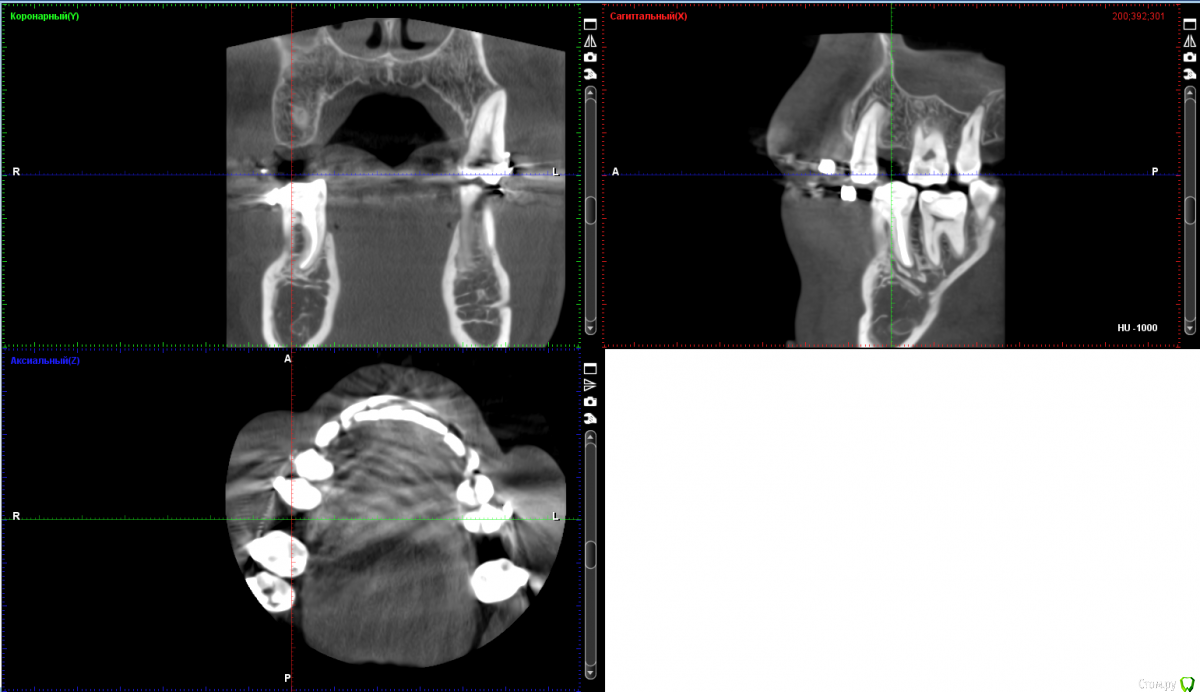

Bors Опубликовано 1 декабря, 2019 Автор Поделиться Опубликовано 1 декабря, 2019 по высоте хватает, ширину нужно смотреть на Кт (качать весь архив не буду) покажите срезы областей интересаСрезы сам не делал, так как не знаю насколько правильными они будут. Прикрепляю то, что получилось. как правило не влияетЯсно. Просто частенько проскакивает в описаниях тех или иных моделей информация о том, что это идеальный вариант при недостатке костной ткани и т.п. Не совсем понятно стоит ли переплачивать за тот же Nobel или выбрать что-то дешевле. Хочется поставить и забыть на всю жизнь про этот зуб. Ссылка на комментарий

red_butler Опубликовано 1 декабря, 2019 Поделиться Опубликовано 1 декабря, 2019 костная пластика не нужна, разве что небольшой закрытый синуслифтинг слева Ссылка на комментарий

Irouil Опубликовано 3 декабря, 2019 Поделиться Опубликовано 3 декабря, 2019 Что касается синус-лифтинга, то по 26-му зубу мне сообщили, что он действительно не нужен, а вот по 16-му что-то вроде пограничного положения. Все наоборот. Но синус лифт там требуется минимальный. Астра тёк прекрасные имплантаты Ссылка на комментарий